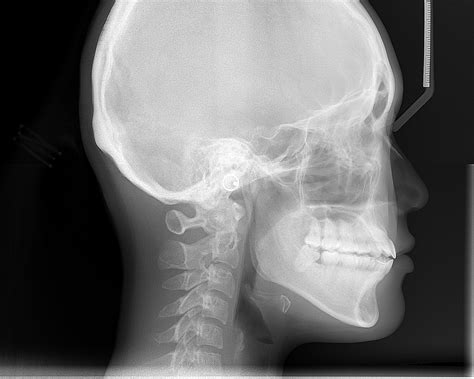

A Cephalometric X Ray is a specialized type of radiograph used to analyze the relationship between the teeth and the jaw. It provides a two-dimensional view of the skull, focusing on the facial bones and teeth. This imaging technique is invaluable for diagnosing and treating various orthodontic conditions, including malocclusions, jaw discrepancies, and facial asymmetries.

The patient’s head is positioned so that the Frankfort plane (a line drawn from the top of the ear canal to the bottom of the eye socket) is parallel to the floor. This ensures that the X-ray beam passes through the skull at the correct angle, providing an accurate image of the facial bones and teeth.

Once the X-ray is taken, the image is developed. In traditional film-based systems, the film is processed in a darkroom. In digital systems, the image is instantly available on a computer screen. The orthodontist then reviews the image to assess the patient’s dental and skeletal structures.